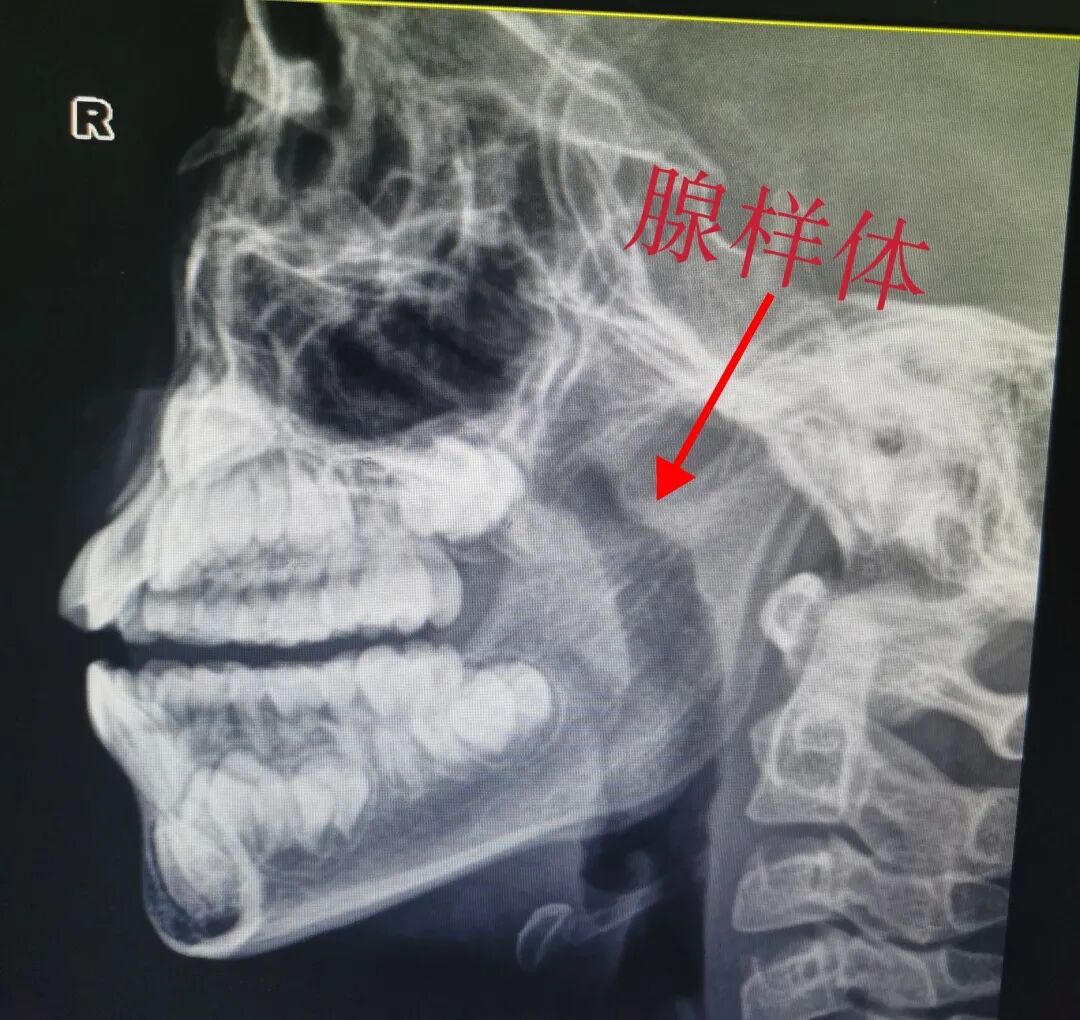

让我们再来看一个鼻炎合并腺样体肥大患儿DR片的对比。

治疗前